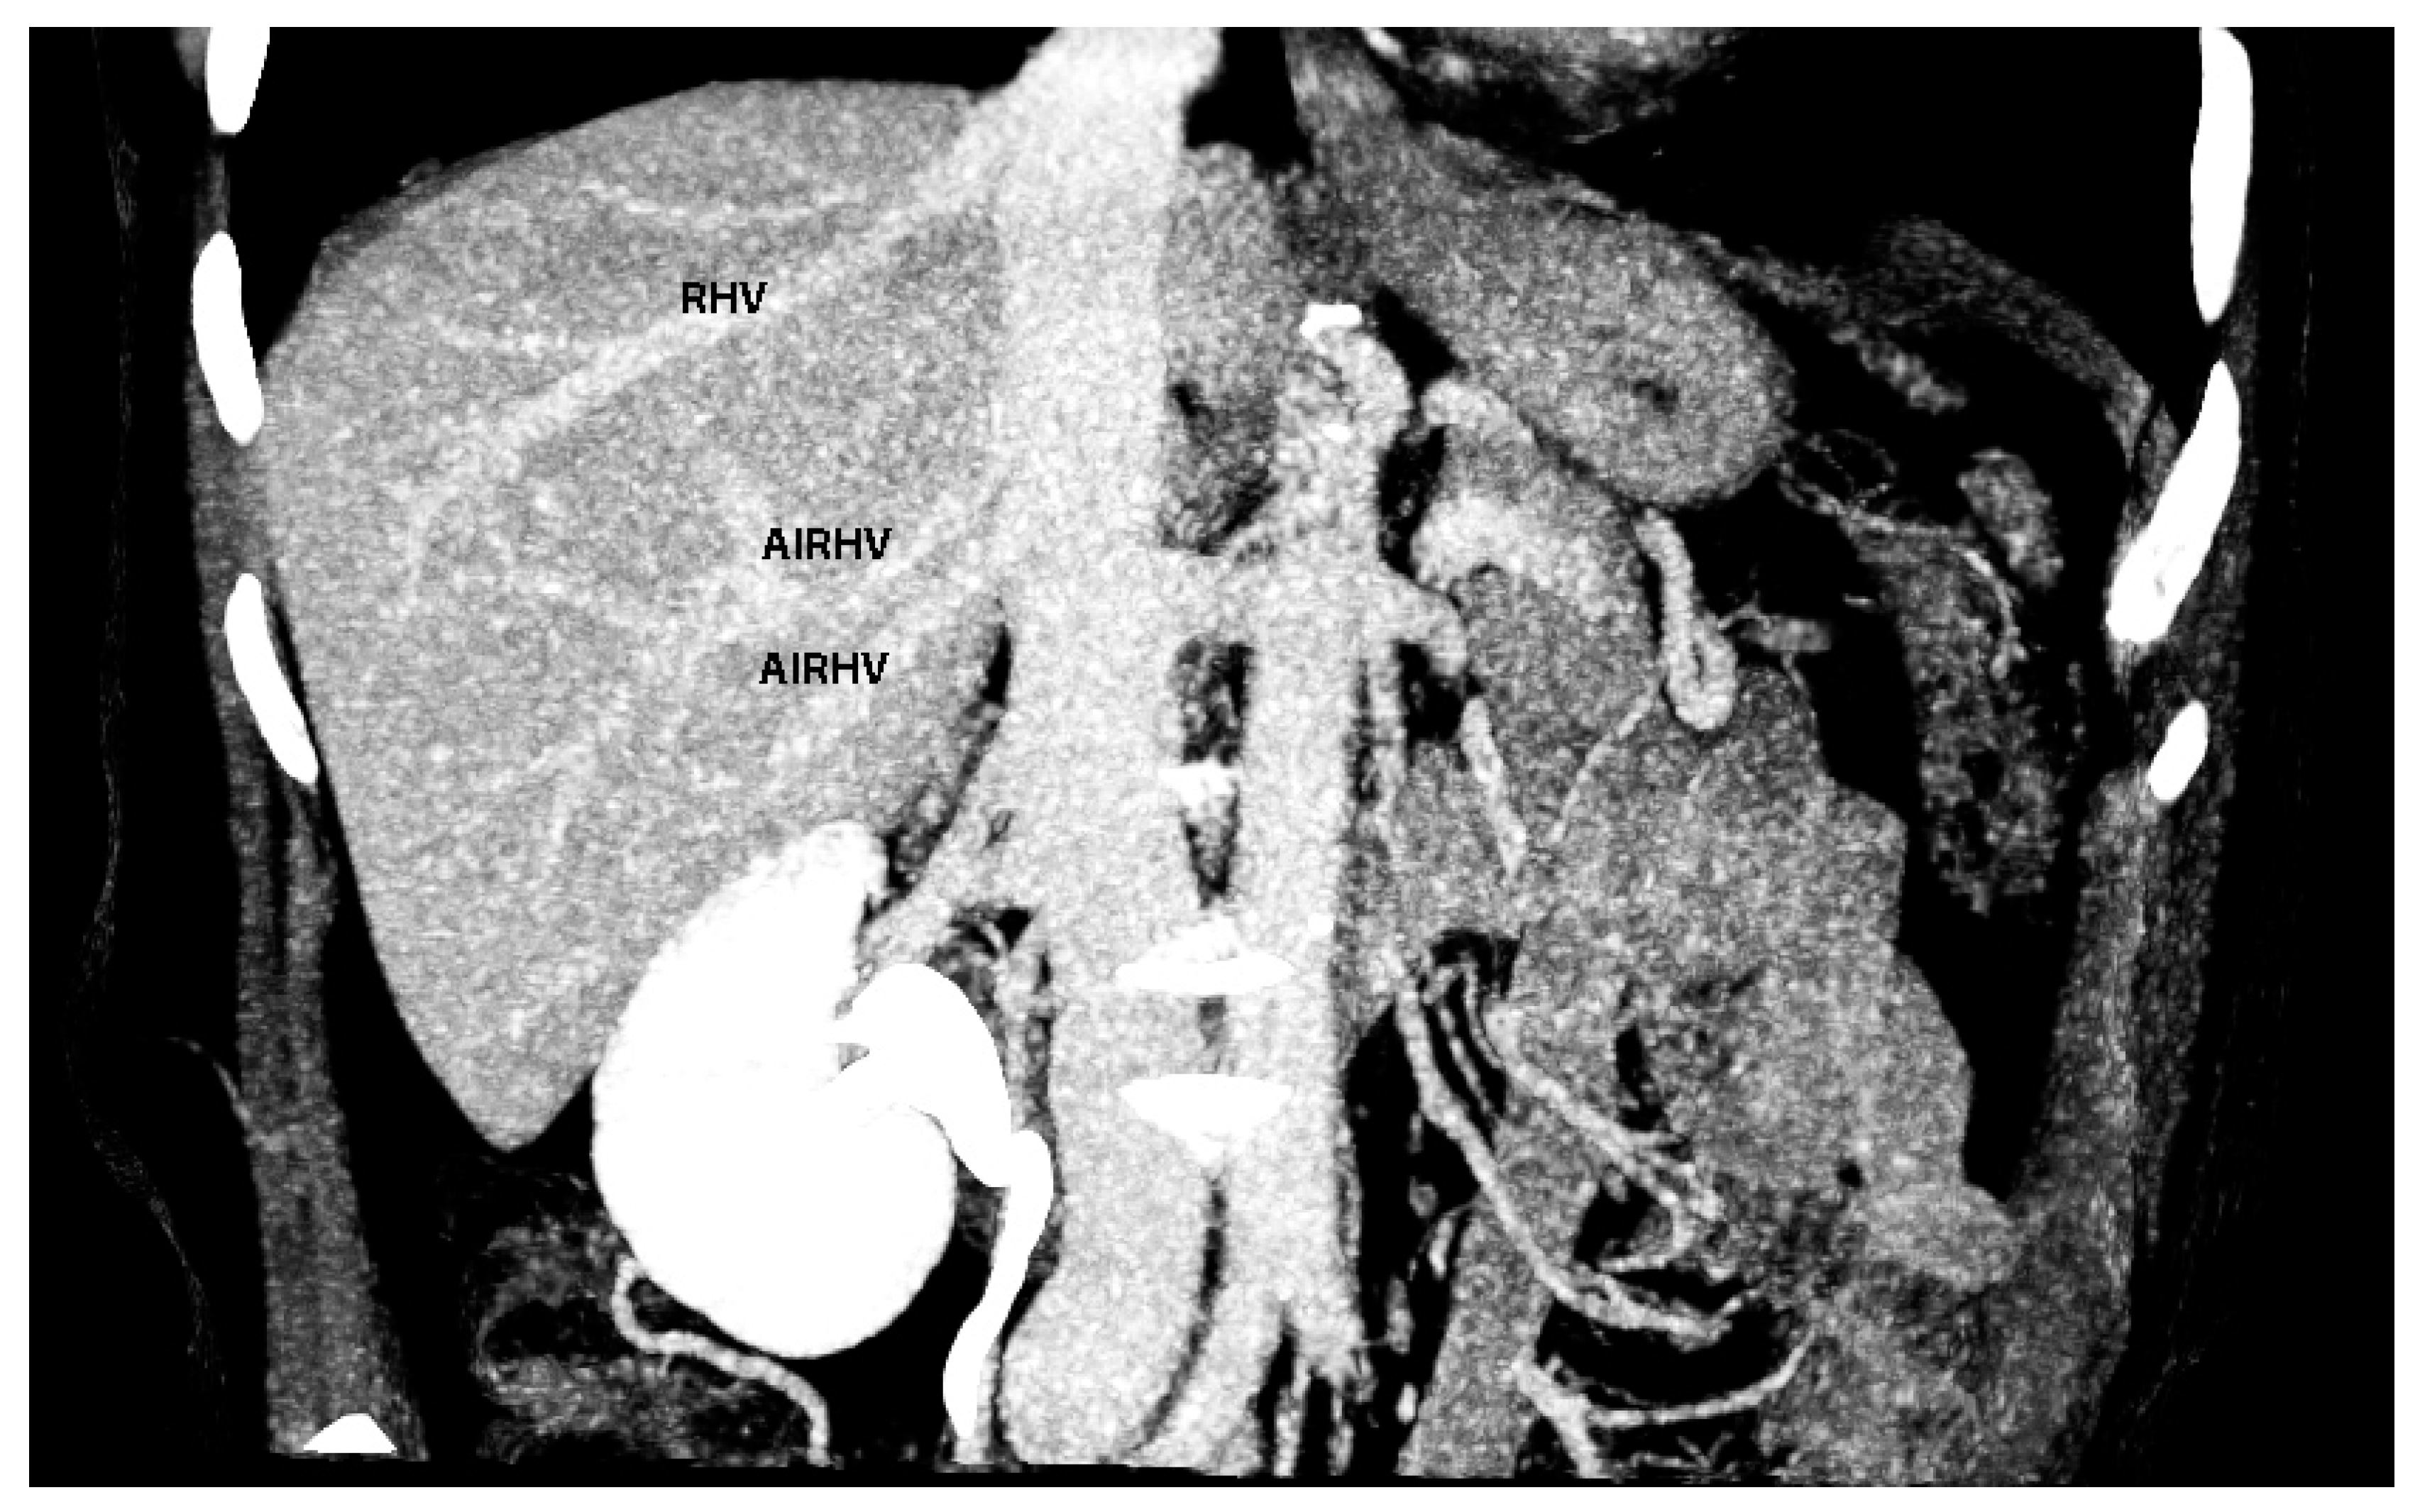

7. Macroscopic and Microscopic Anatomy of the Liver—One Entity

- Sureka, B.; Sharma, N.; Khera, P.S.; Garg, P.K.; Yadav, T. Hepatic vein variations in 500 patients: Surgical and radiological significance. Br. J. Radiol. 2019, 92, 20190487. [Google Scholar] [CrossRef] [PubMed]

- Shilal, P.; Tuli, A. Anatomical variations in the pattern of the right hepatic veins draining the posterior segment of the right lobe of the liver. J. Clin. Diagn Res. 2015, 9, AC08-12. [Google Scholar] [CrossRef]

- Cawich, S.O.; Naraynsingh, V.; Pearce, N.W.; Deshpande, R.R.; Rampersad, R.; Gardner, M.T.; Mohammed, F.; Dindial, R.; Barrow, T.A. Surgical relevance of anatomic variations of the right hepatic vein. World J. Transplant. 2021, 11, 231–243. [Google Scholar] [CrossRef]